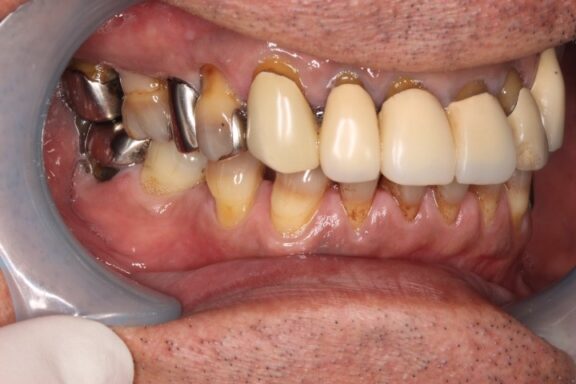

本日は、60歳代男性患者様のケースです。

前歯には、過去に他院様にてプラスチックが前面に貼り付けてある「前装冠」という保険診療のクラウン(被せ物)が施されている状態でした。

奥歯には複数の歯に銀を主成分とするメタル修復がされている状態でした。

今回は審美修復含めて、全体的に綺麗にしていく計画を患者様と一緒に建てさせていただきました。